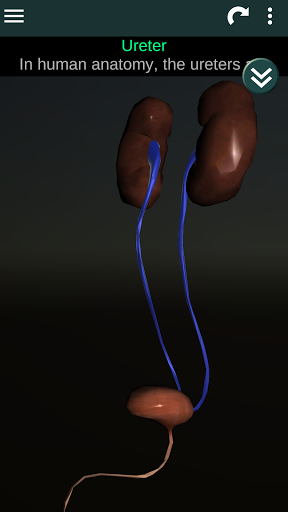

Shows a 3D anatomical model of the main organs of the human body and a description of each one.

* Easy to access and navigate (zoom, 3D rotation).

* Descriptions of each organ.